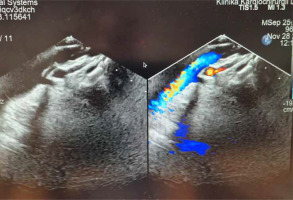

Unfortunately, after 1.5 years, the symptoms recurred with worsening cyanosis, decreased exercise tolerance, and frequent infections with bronchial casts and productive cough. Repeated echocardiography revealed dilated IVC and hepatic veins, with a wide, unrestricted interatrial connection and a patent fenestration with a stent in place. The Fontan tunnel appeared wide. Following anterior leaflet prolapse, mild to moderate tricuspid regurgitation (grade I/II) was noted. TAPSE measured 9.6–9.7 mm, indicating mildly reduced right ventricular systolic function. The right ventricular free wall was thickened, but overall global and segmental function was good. There was trace aortic valve regurgitation, with the neo-aorta measuring approximately 20 mm in diameter. The superior cava and brachiocephalic veins were widened, and a broad connection was observed between the superior systemic veins and the pulmonary arteries. The stent in the left pulmonary artery (LPA) measured 8–8.5 mm in diameter, while the right pulmonary artery (RPA) measured 8–8.2 mm. The neo-aortic arch, including the isthmus, had a peak velocity ranging from 1.7 to 1.9 m/s. In the ultrasound of the abdomen, an enlarged liver with a fibrotic-like structure was depicted, indicating fibrotic remodelling of the liver.

The subsequent heart catheterisation revealed a typical aorta without significant collateral vessels to the lungs. The innominate vein measured 8 mm in diameter, with no notable veno-venous anastomoses. The RPA measured 8.1 mm, while the LPA was approximately 8.5 mm in diameter and had undergone stent re-dilatation to 10 mm. The Fontan tunnel was dilated to about 3 cm, and the fenestration with a stent showed right-to-left shunting (Figure 4). Haemodynamic data showed a superior vena cava pressure of 20 mm Hg (oxygen saturation of 68%) and an IVC pressure of 22 mm Hg (oxygen saturation of 57%). The mean Fontan tunnel pressure was 20 mm Hg, and right ventricular pressures were 75/15 mm Hg. The RPA pressure was 20 mm Hg (oxygen saturation of 65%), while the LPA pressure was 18 mm Hg (oxygen saturation of 68%). The mean left atrial pressure was 16 mm Hg, with an oxygen saturation of 95%. The aortic pressure was 85/52 mm Hg, with an oxygen saturation of 85%. The calculated Qp : Qs ratio was 0.79, indicating reduced pulmonary flow. PVR was 3.8 Wood units (PVR index 2.28 Wood units·m²), and SVR was 38.13 Wood units, indicating significant haemodynamic strain typical of failed Fontan physiology.

Figure 4

Angiography of the pulmonary arteries and Fontan tunnel. The right pulmonary artery measured 8.1 mm and was dilated with the 12 mm balloon, and the left pulmonary artery had undergone stent re-dilatation to 10 mm. The Fontan tunnel was dilated to 3 cm in the central portion, and the fenestration with a stent showed right-to-left shunting. The hepatic veins and inferior vena cava were also significantly widened